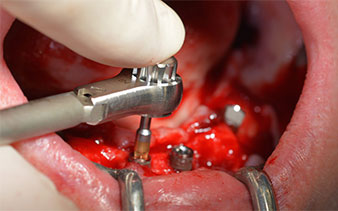

Zunächst wurde das Foramen mentale als limitierende anatomische Struktur dargestellt und die krestale Kortikalis mit dem geraden Handstück und einem großen Rosenbohrer geglättet (Abb. 4).

Unterkiefer-Restbezahnung

Abb. 4